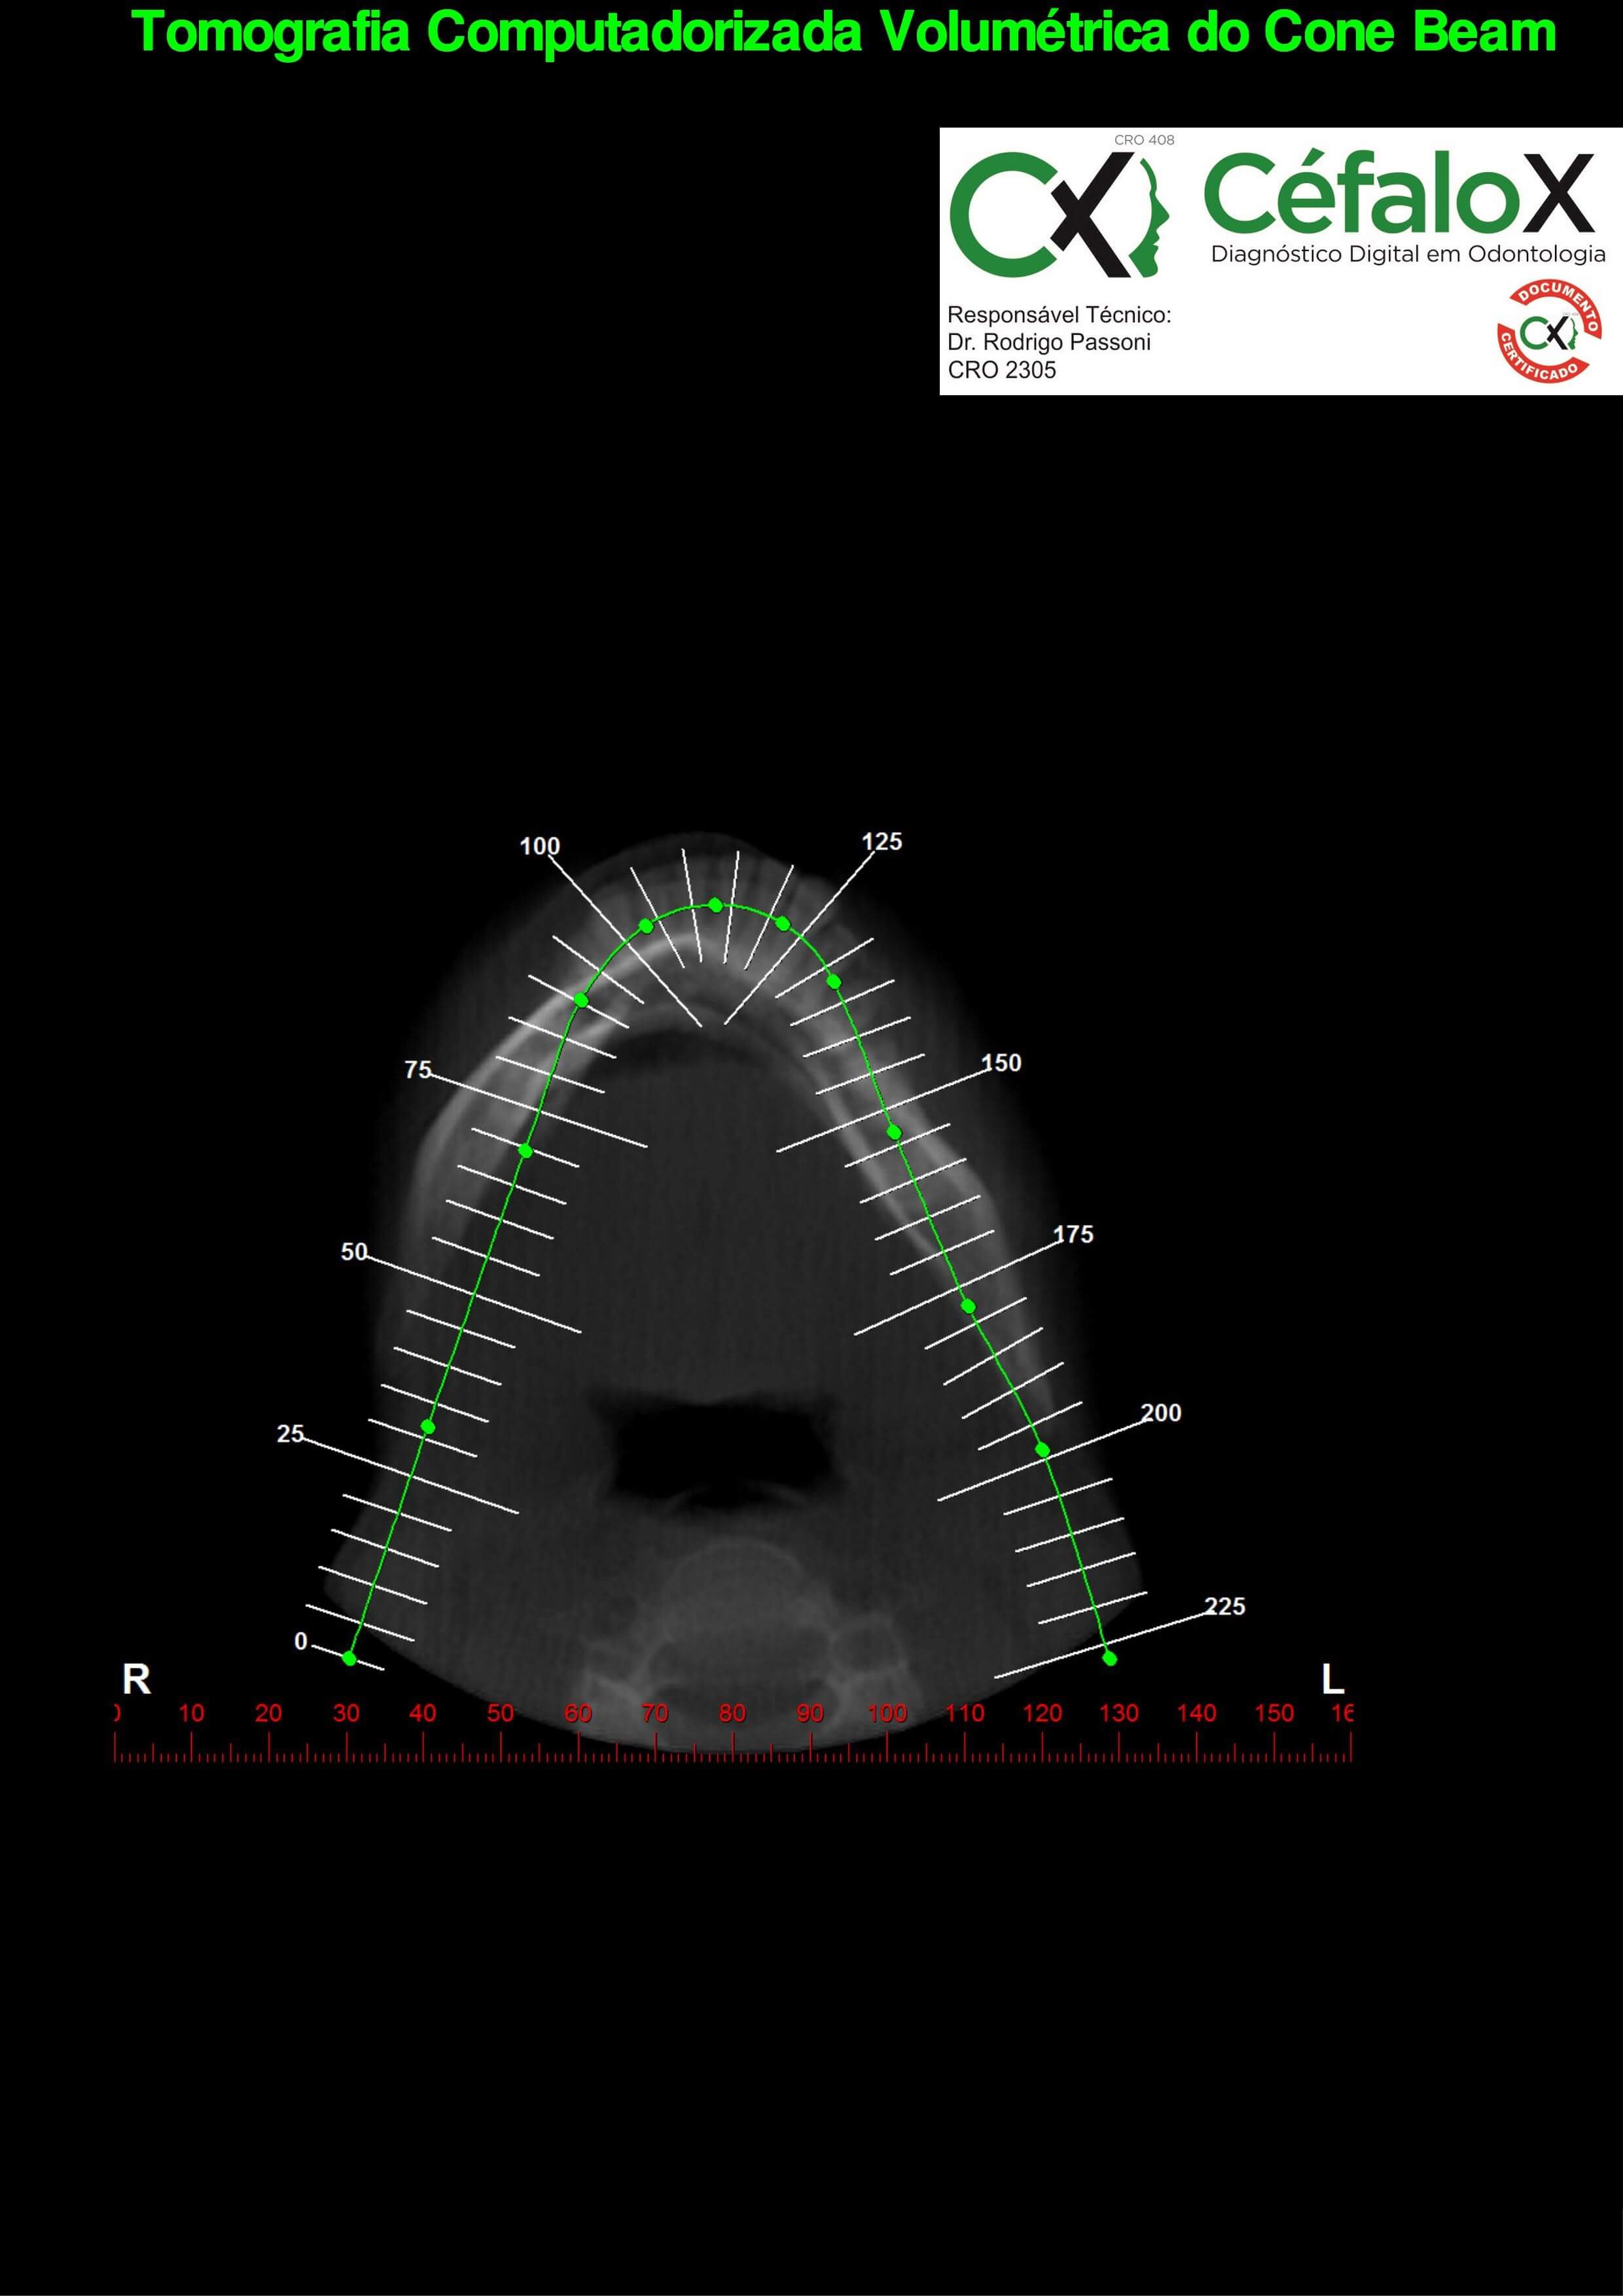

TC de face (do Hióide à Glabela), reconstrução 3D do tecido ósseo, radiografia panorâmica, telerradiografia lateral com traçado, cortes transversais e axial de maxila e mandíbula e arquivo DICOM- entregue em pasta de Pvc.

TC de face (do Hióide à Glabela), reconstrução 3D do tecido ósseo, radiografia panorâmica, telerradiografia lateral e frontal com traçado, cortes transversais e axial de maxila/mandíbula e arquivo DICOM – entregue em pasta de Pvc.

TC de face (do Hióide à Glabela), reconstruções 3D do tecido mole/ósseo/vias aéreas, radiografia panorâmica, telerradiografia lateral e frontal com traçado, cortes transversais e axial de maxila/mandíbula, ATM e arquivo DICOM – entregue em pasta e caixa de Pvc.